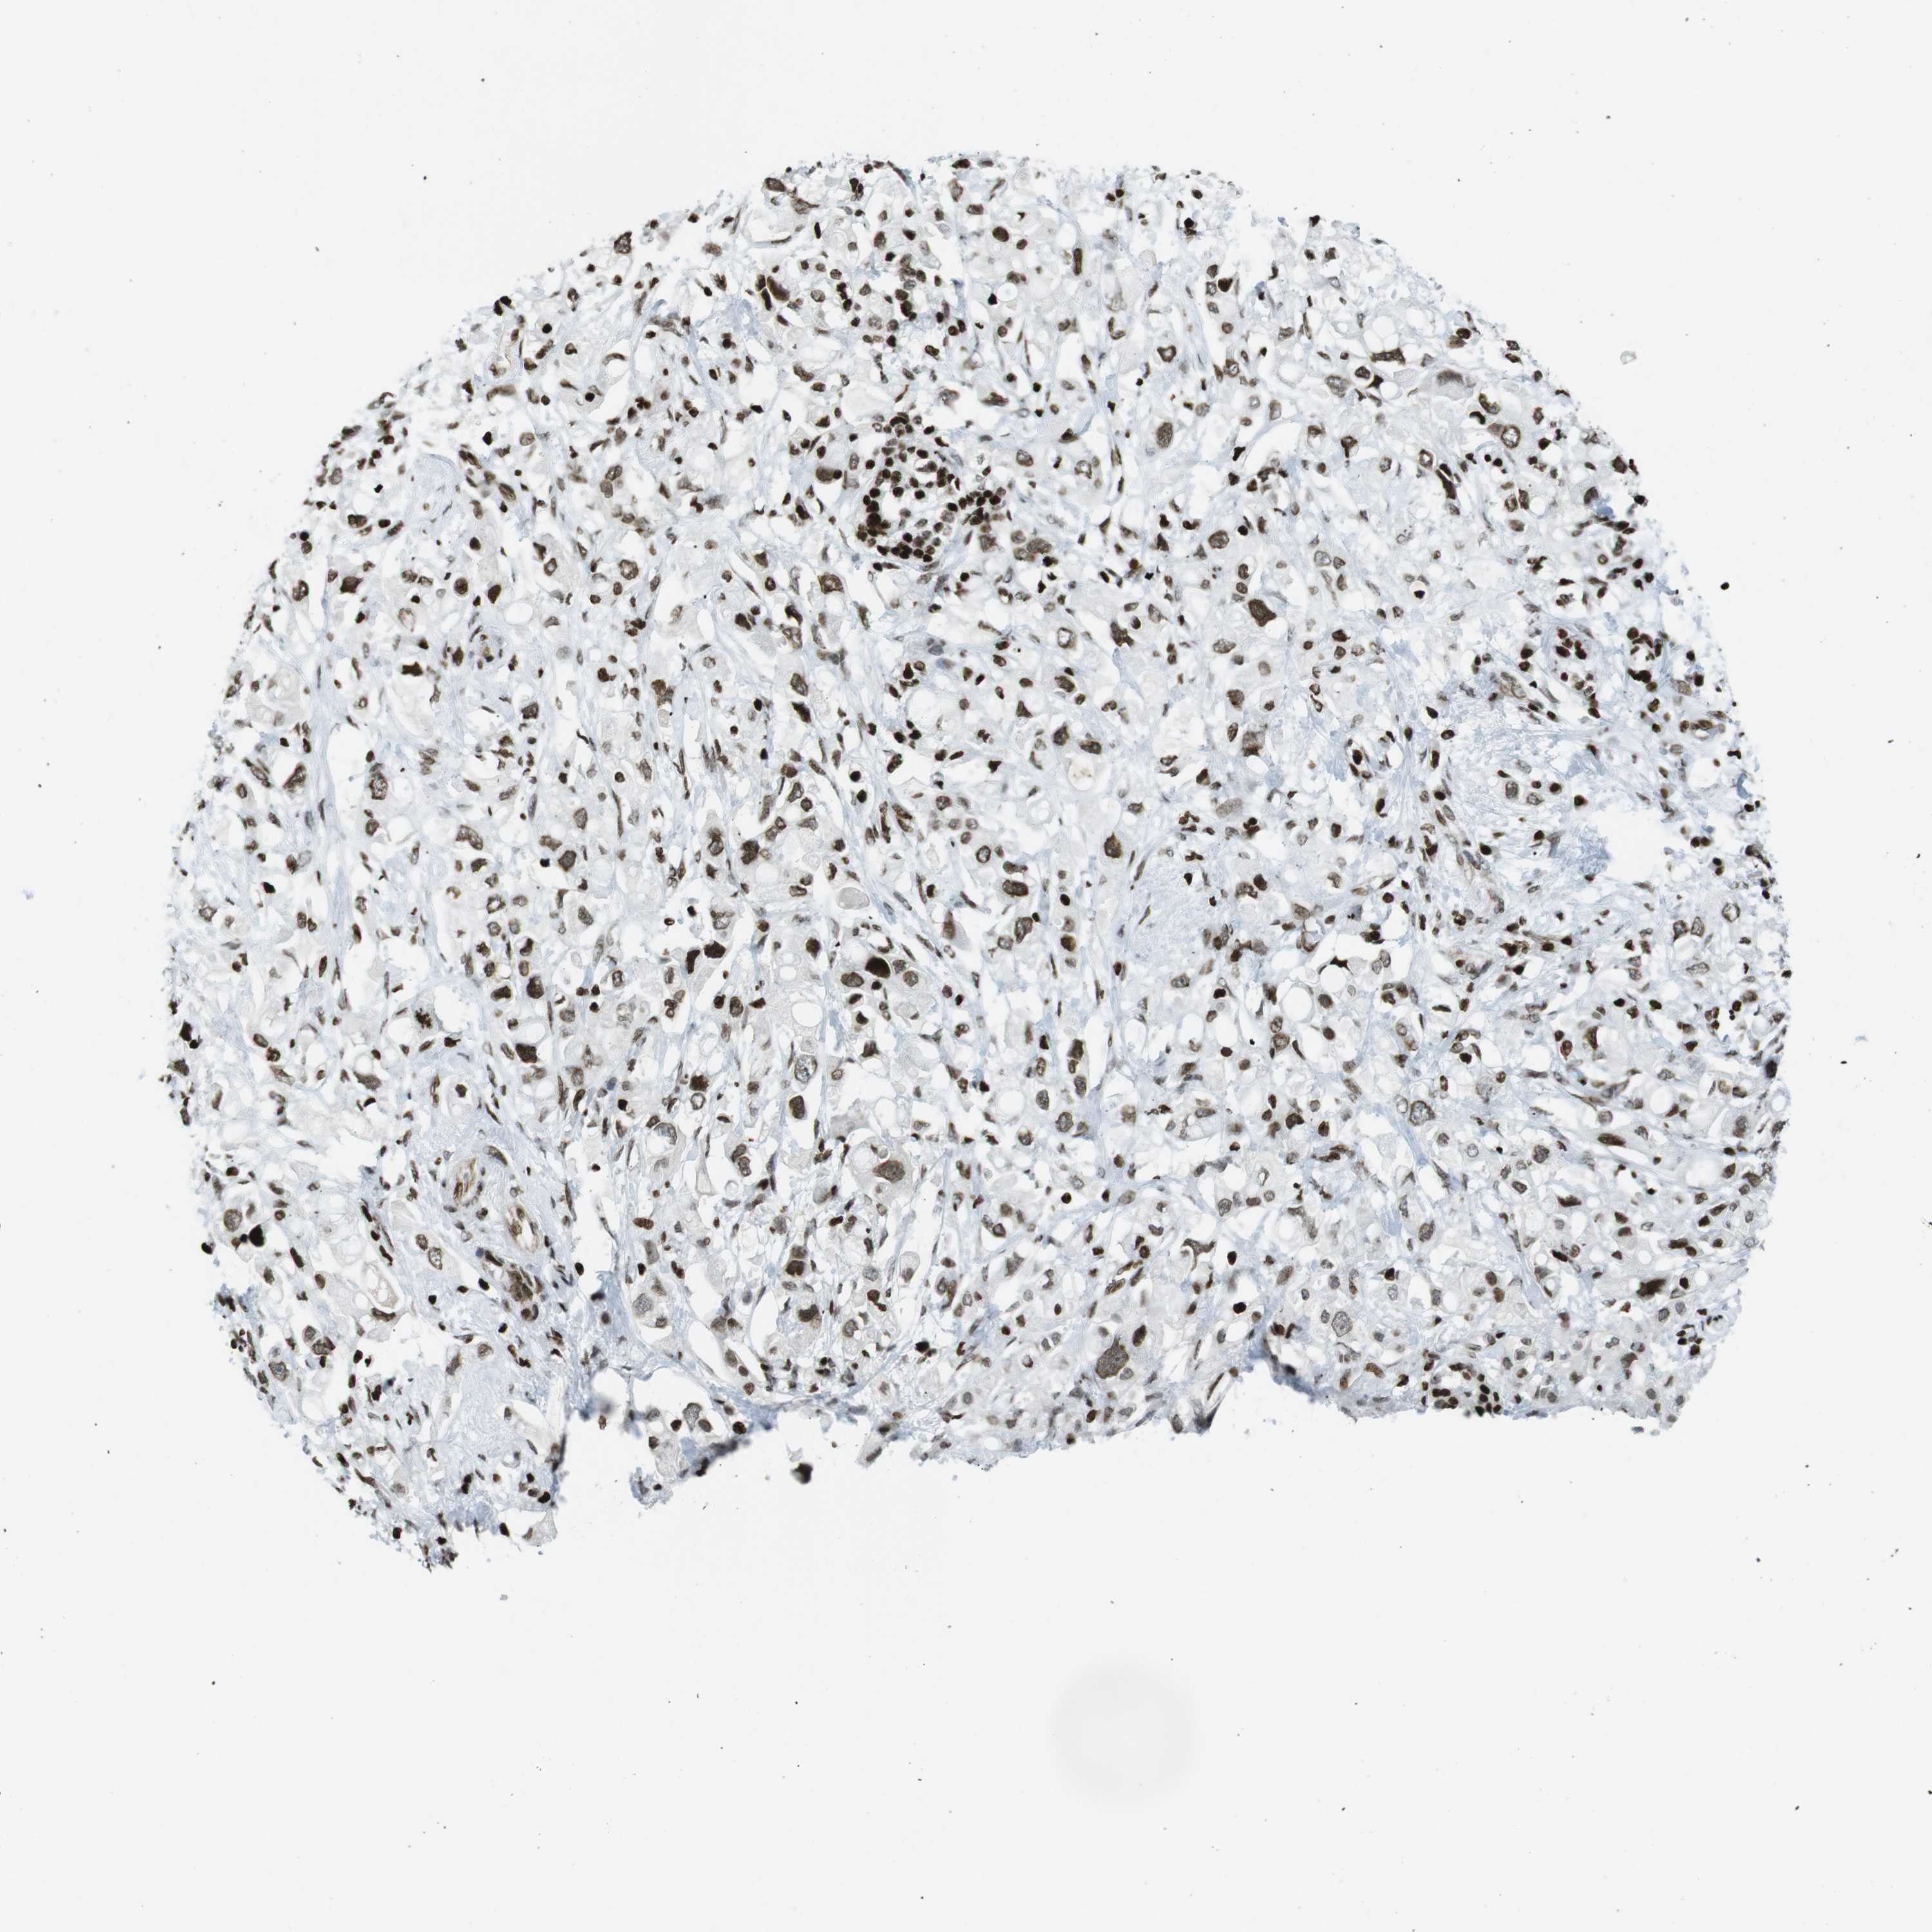

PANCREATIC CANCER - Protein expressioni

A mouse-over function shows sample information and annotation data. Click on an image to view it in a full screen mode. Samples can be filtered based on level of antibody staining by selecting one or several of the following categories: high, medium, low and not detected. The assay and annotation is described here.

Note that samples used for immunohistochemistry by the Human Protein Atlas do not correspond to samples in the TCGA dataset.

Antibody stainingi

Antibody staining in the annotated cell types in the current human tissue is reported as not detected, low, medium, or high, based on conventional immunohistochemistry profiling in selected tissues. This score is based on the combination of the staining intensity and fraction of stained cells.

Each image is clickable and will lead to virtual microscopy that enables deeper exploration of all samples and also displays staining intensity scores, fraction scores and subcellular localization as well as patient and tissue information for each sample.

Antibody HPA041189

Antibody CAB012242

Staining

High

Medium

Low

Not detected

Intensity

Strong

Moderate

Weak

Negative

Quantity

>75%

75%-25%

<25%

None

Location

Nuclear

Cytoplasmic/membranous

Cytoplasmic/membranous,nuclear

Adenocarcinoma, NOS

Adenocarcinoma, metastatic, NOS